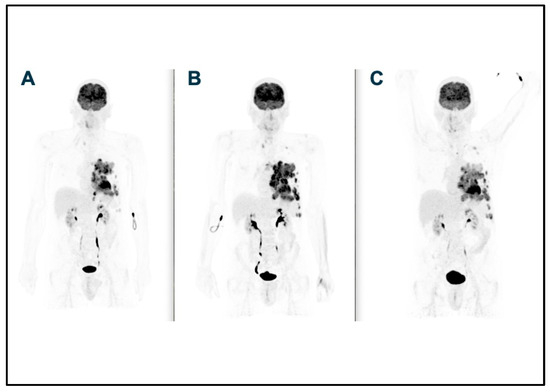

2. Case Report